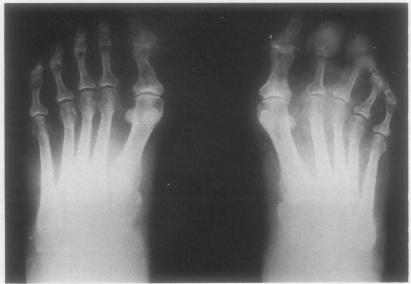

Investigation and management of gout in the young and the elderly.

Ann Rheum Dis. 1991 Apr;50(4):263-6. doi: 10.1136/ard.50.4.263.